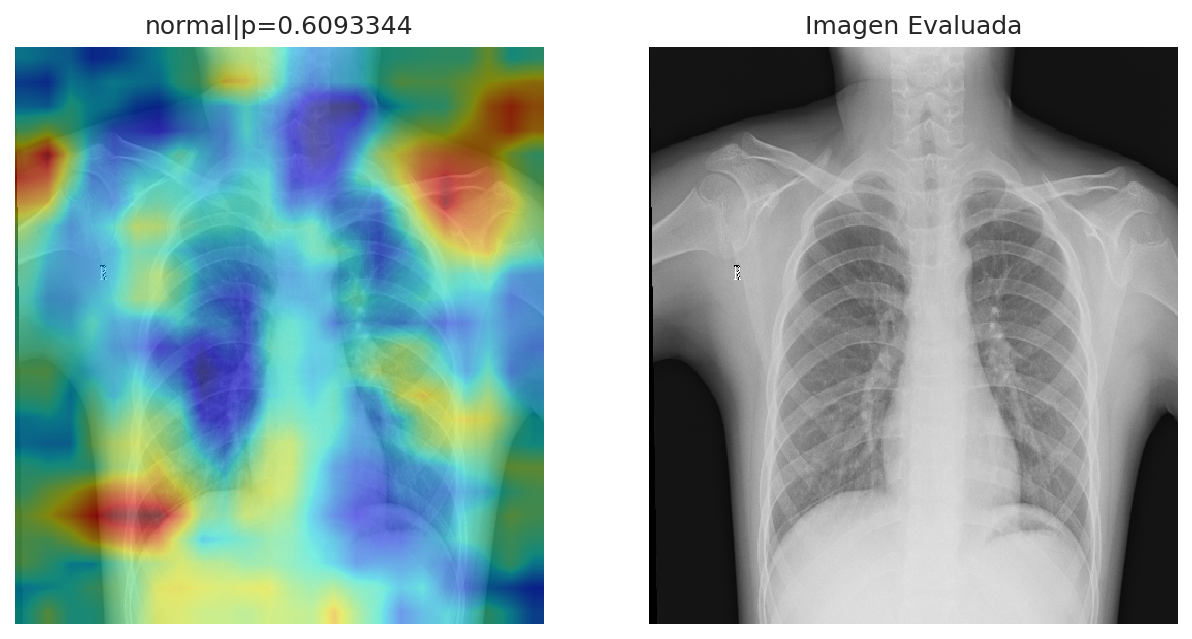

The diagnosis discards the presence of pneumonia in the patient. From the analysis, the patient present a normal state, with a 60.93% of confidence. Whereas the probability of having pneumonia is: 39.07%. The distribution for both states can be observed in the plot.

The zonal analysis shown, which areas from the image, where used to carry on the diagnosis. This represent the zones where the algorithm detect pneumonia or a normal state. The cold colors, represent the zones, which have a probability of having a normal state, whereas the warm colors represent the probability of pneumonia in such zones. This information is intended to bring support as evidence about the diagnosis. Since this application is under development, some zones mark areas out of the main image. This will be improved in the next iterations. To see the analysis in more detail, click on the image to zoom in.